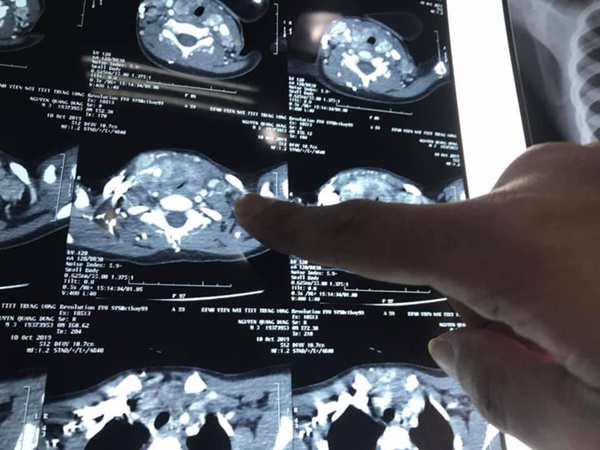

Kết quả sau khám bé D được chẩn đoán ung thư tuyến giáp với mức độ di căn nhiều hạch cổ 2 bên. Khối u đã phát triển lớn chèn ép khí quản gây khó thở.

Khối u tuyến giáp của bệnh nhi, ảnh BVCC.

Mức độ di căn của bệnh nhi lan rộng vào cả dây thần kinh quặn ngược, tĩnh mạch cảnh và khí quản gây đè bẹp khí quản khiến cho việc đặt nội khí quản trong quá trình gây mê, quá trình bóc tách, nạo các nhóm hạch ở vùng cổ hết sức khó khăn.

"Trong quá trình phẫu thuật, hạch di căn của bé D đã được đem đi thực hiện cắt lạnh tế bào và cho kết quả ung thư tuyến giáp thể tủy. Đây được coi là thể ít gặp đối với những bệnh nhân nhỏ tuổi trong ung thư tuyến giáp và chỉ có khoảng 5% trường hợp mắc phải", bác sĩ Lương thông tin.